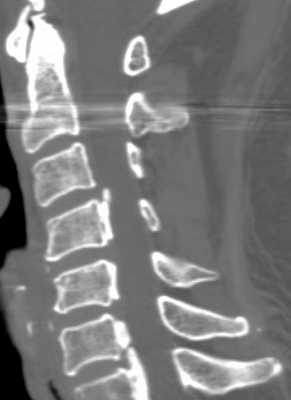

МРТ позвоночника. Сагиттальная Т2-взвешенная МРТ шейного отдела позвоночника. Стеноз позвоночного канала обызвествленной задней продольной связкой.

КТ шейного отдела позвоночника. Реконструкция в сагиттальную плоскость. Оссификация задней продольной связки.